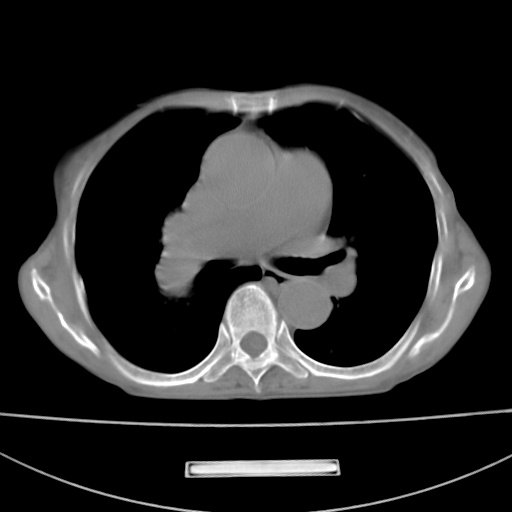

患者 女 67岁,反复咳嗽咳痰2年,加重伴喘及双下肢浮肿1月

陈旧性肺结核、慢性支气管炎、支气管扩张症、肺心症、肺动脉高压。

诸大血管及f肺门血管增粗迂曲.左下肺多发薄壁空腔影.部分非也透亮度增高.薄曾扫描可区分肺气肿类型.考虑1.慢性支气管炎 2.左下肺支气管扩张 3.肺气肿 4 肺动脉高压5.是否有先心病病史

考虑1.慢性支气管炎 2.左下肺支气管扩张 3.肺气肿 4 肺动脉高压

慢支炎、肺气肿、双肺感染、左下囊状支扩。

慢支、肺气肿、肺动脉高压;左下肺囊状支扩并粘液栓形成。